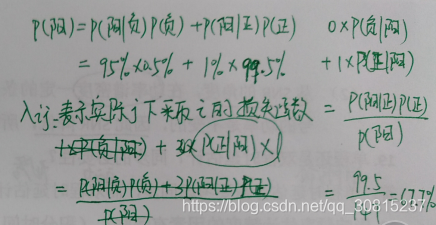

实例:有一家医院为了研究癌症的诊断,对一大批人作了一次普查,给每人打了试验针,然后进行统计,得到如下统计数字:

①这批人中,每1000人有5个癌症病人;

②这批人中,每100个正常人有1人对试验的反应为阳性,

③这批人中,每100个癌症病人有95人对试验的反应为阳性。

假设将正常人预测为正常人和将癌症患者预测为癌症患者的损失函数均为0,将癌症患者预测为正常人的损失函数为3,将正常人预测为癌症患者的损失函数为1.

现在某人试验结果为阳性,根据最小风险贝叶斯决策理论,将此阳性患者预测为患癌症的风险概率为(67.7% )。

患癌症的风险概率:不患癌症概率*(不患癌症却被判为癌症的损失系数1)+患癌症概率*(患癌症被判为癌症的损失系数0)

同理:将此阳性患者预测为正常的风险概率为:不患癌症概率*(不患癌症被判不患癌症的损失系数0)+患癌症概率*(患癌症被判为不患癌症的损失系数 3)